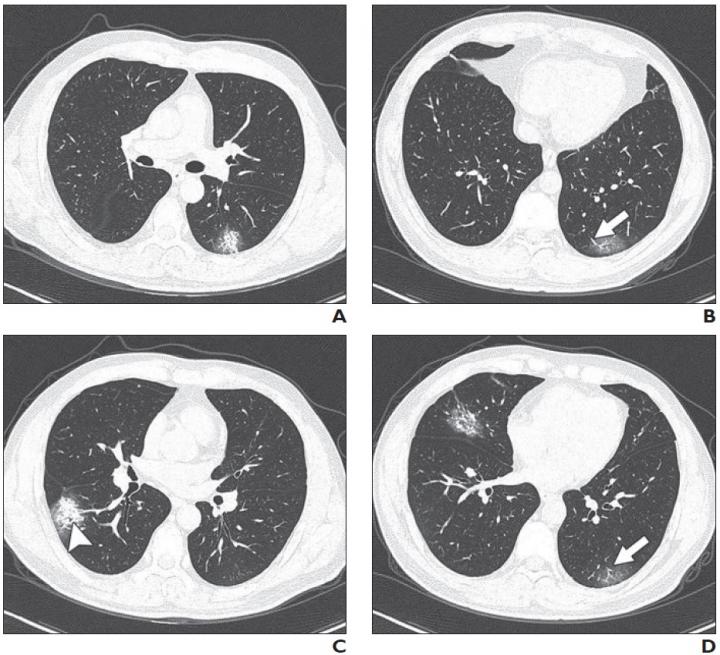

37-Year-Old Man with Confirmed Coronavirus Disease (COVID-19), Common Type (IMAGE)

Patient had short-term exposure history to Wuhan and onset symptoms of fever (38°C) and cough. CT was performed on day of admission. A-D, CT images show bilateral multifocal ground-glass opacities (GGO) and mixed GGO and consolidation lesions. Traction bronchiectasis (arrowhead, C) and vascular enlargement (arrow, B and D) are also present. CT involvement score is 5.